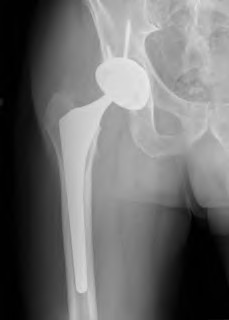

A 72-year-old female falls and sustains a periprosthetic femur fracture around her cementless total hip arthroplasty. Radiographs reveal a fracture extending just distal to the tip of the stem. The stem is radiographically loose, but there is excellent proximal and distal bone stock. According to the Vancouver classification, what is the fracture type and the recommended surgical treatment?